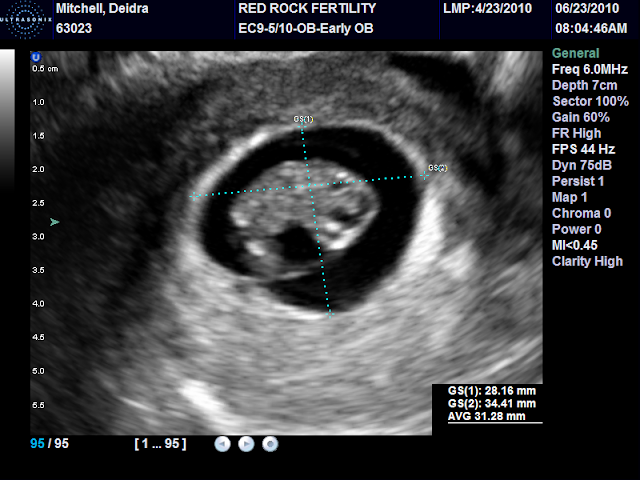

Oh wait no we aren't having "A" baby we are having two babies. YIPPEE! I can't hardly believe it and I find myself looking at these pictures over and over just to make sure I am not crazy. We are due on January 28, 2011. Please pray for us as we are still early in this need to make it through the first trimester. Both babies had great heart beats. Baby A's was 135 and Baby B's was 122. Baby B's sac was pretty small so I was advised to drink lots and lots of water and to take it easy which is what I am doing. EEEEEEEEEEEEEEEEEK! Zack thinks it is a brother and a sister but we will have to wait till the day of delivery because we aren't finding out.